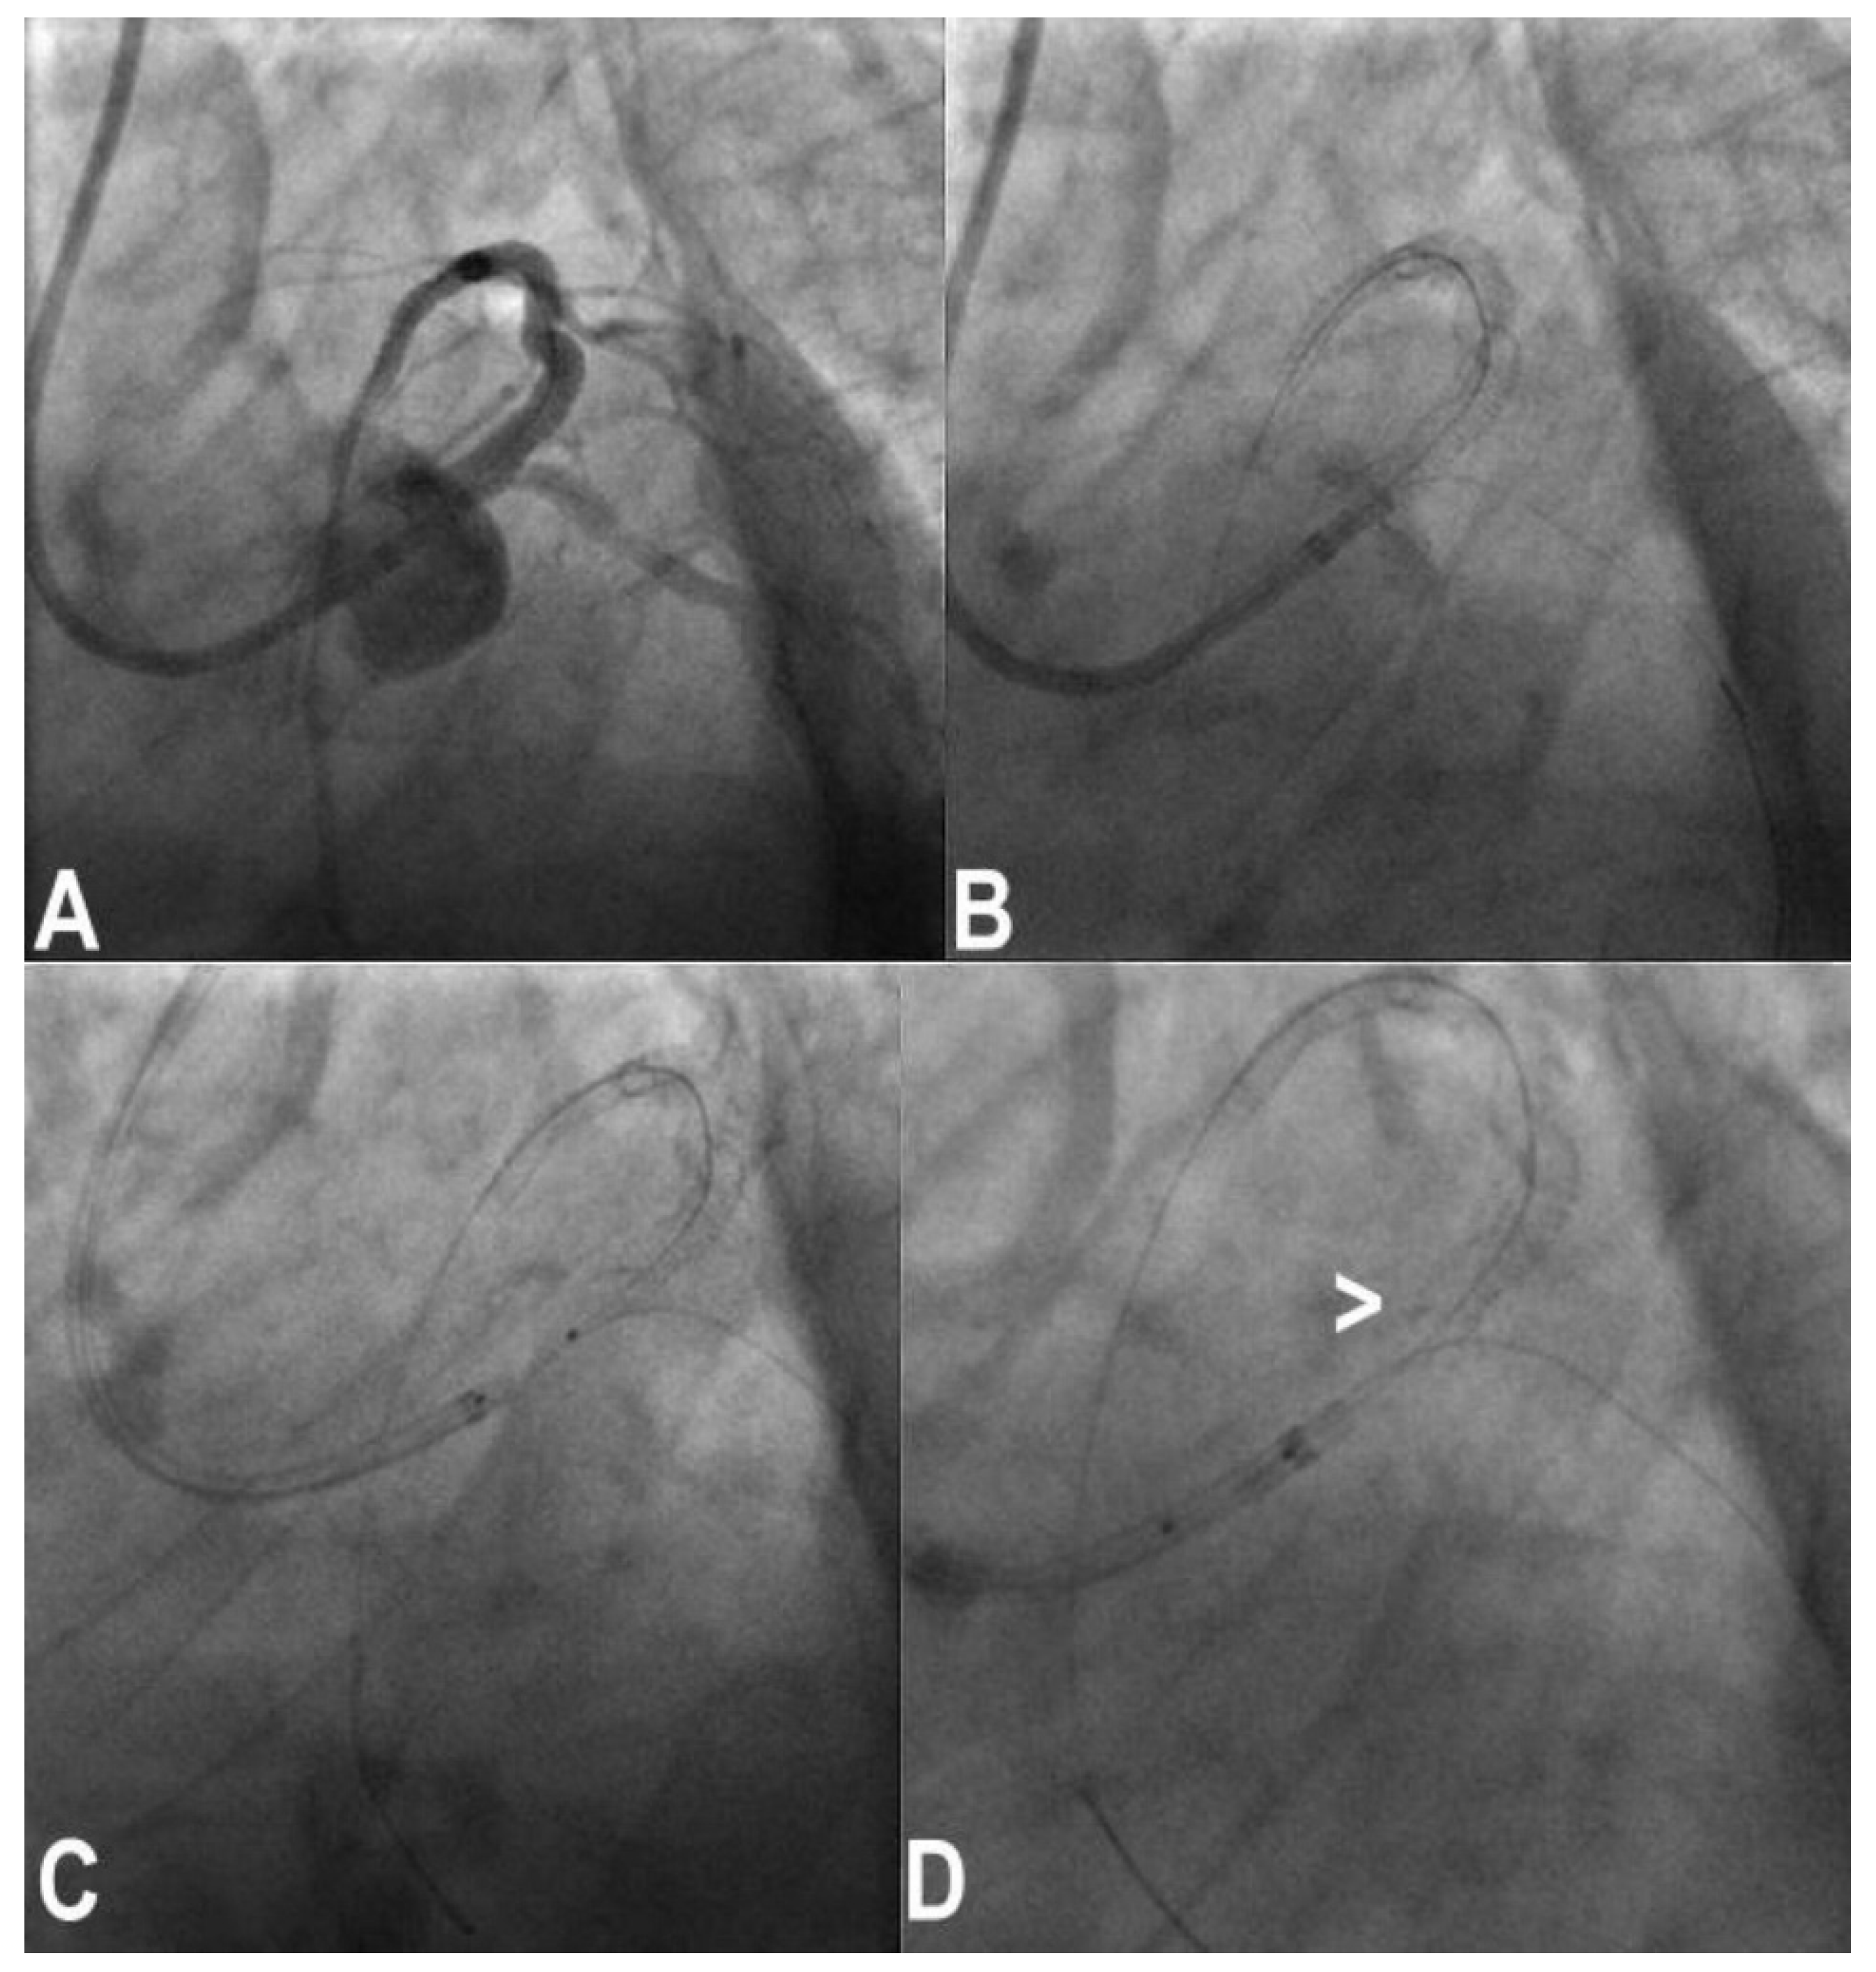

3.9. Balloon Entrapment

3.10. Device Entrapment